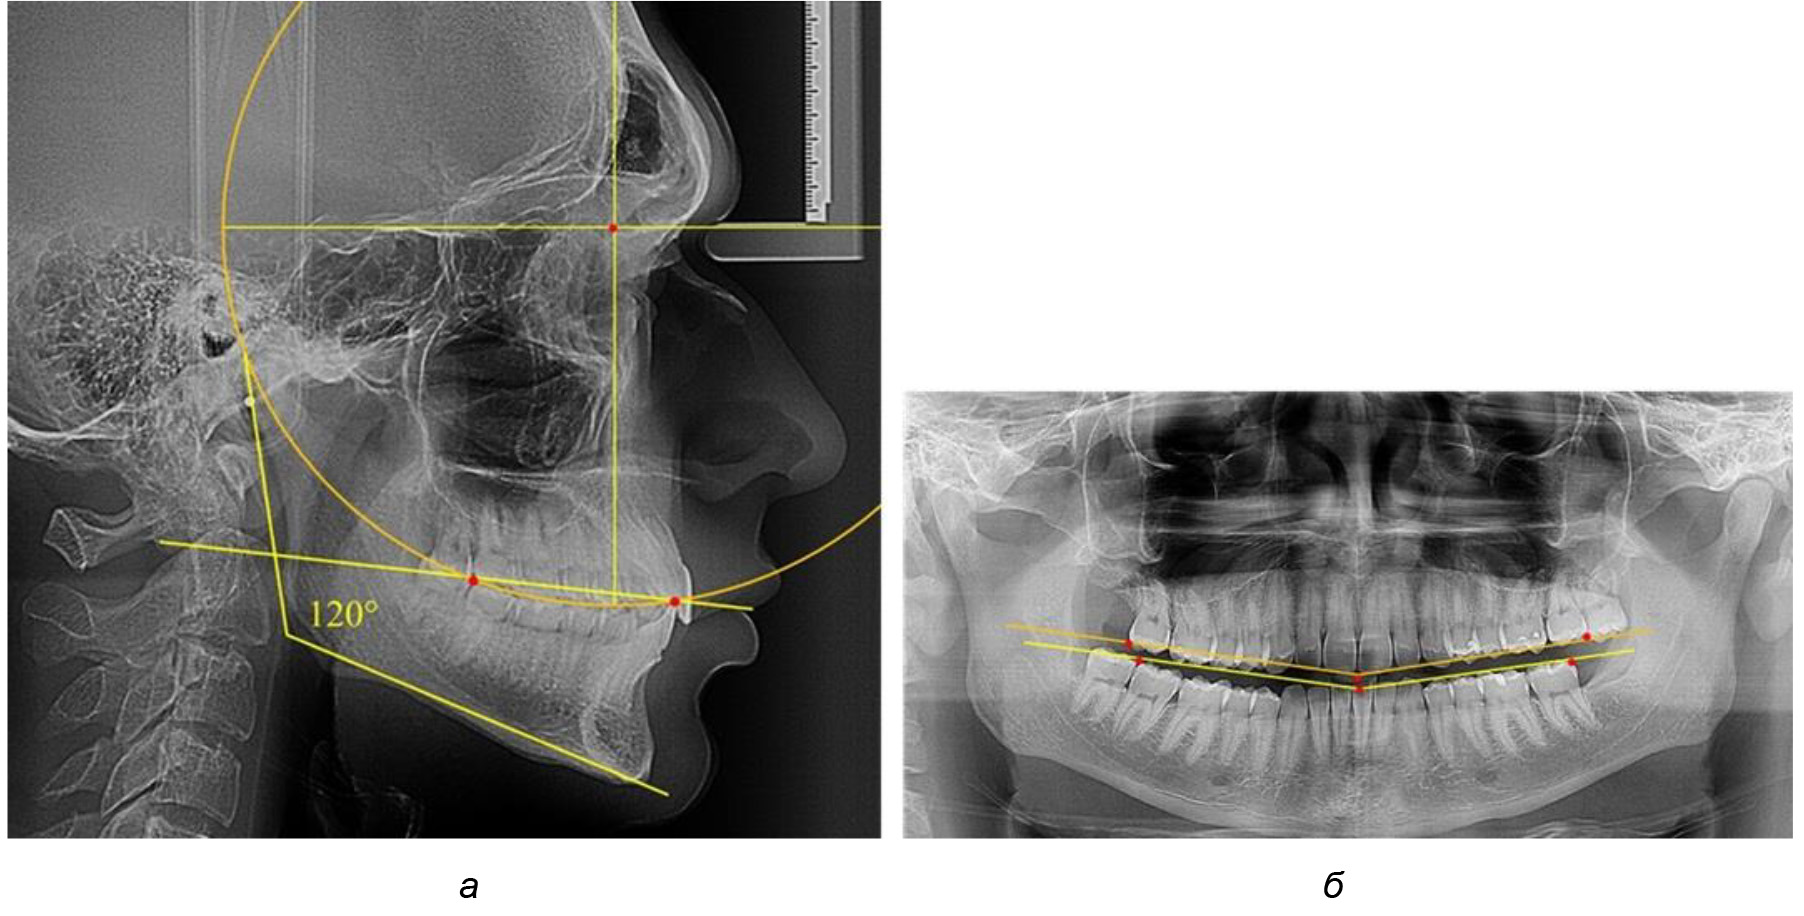

При анализе латеральных ТРГ устанавливали реперный окклюзионные точки в переднем и боковом отделе. Передняя точка устанавливалась на режущем крае нижнего медиального резца, которую в клинике ортодонтии обозначают как vPOcP. Дистальная точка второго нижнего моляра обозначалась как hPOcP. Измеряли расстояние между окклюзионными точками, что определяло сагиттальный размер окклюзионной линии. Использование программ PowerPoint позволило проводить окружность, проходящую по линии смыкания зубов через окклюзионные точки. Измеряли радиус окружности. Учитывая вариабельность размеров окклюзионной линии и радиуса окружности, определяли относительный показатель через отношение радиуса круга к длине сагиттального размера окклюзионной линии. Глубину окклюзионной кривой измеряли от точки наибольшей выпуклости до окклюзионной линии (рис. 1). На ортопантомограмме (ОПТГ) также соединяли окклюзионные точки правой и левой стороны и измеряли глубину окклюзионной кривой от точки наибольшей выпуклости до окклюзионной прямой линии. Результаты глубины кривой Spee сравнивали по данным ТРГ и ОПТГ.

Рис. 1. Метод определения кривой Spee на ТРГ (а) и на ОПТГ (б)

Деление величины радиуса круга к длине окклюзионной линии составило 1,623 ± 0,02. Таким образом, для определения радиуса окружности, соответствующей кривизне окклюзионного контура боковой ТРГ, необходимо измерить расстояние между передней и задней окклюзионными точками и последующим умножением полученной величины на число Фибоначчи (рис. 2).

Рис. 2. Особенности кривой Spee на ТРГ (а) и ОПТГ (б) у людей с признаками вертикального роста

На рентгенограммах людей 2-й подгруппы (30 человек с нейтральным типом роста) величина угла нижней челюсти в среднем составила (120,34 ± 2,19) ° и характеризовала нейтральный тип нижней челюсти.

Глубина кривой Spee в среднем по 2-й подгруппе составил (3,54 ± 0,58) мм, что было незначительно меньше, чем при анализе аналогичного показателя 1-й подгруппы.

Достоверных различий с показателями, полученными при анализе ТРГ и ОПТГ, нами не отмечено (р ˃ 0,05). Деление величины радиуса круга к длине окклюзионной линии составило 1,612 ± 0,02, что, так же как и в 1-й подгруппе, было близким по значению к числу Фибоначчи (1, 618).